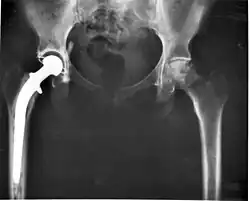

A osteólise pode ser uma resposta autoimune do organismo contra artroplastias de quadril ou joelho. As células que consomem os fragmentos de plástico microscópicos da prótese podem ser interpretados como uma ameaça a ser eliminada e desencadear uma maior reabsorção dos ossos ao redor da prótese após alguns anos de uso.[2] Também pode ser causada por patologias como tumores ósseos, doença de Paget do osso, cistos periósteos ou uma inflamação crônica como osteoartrite.

Geralmente é assintomática, apenas deixando os ossos mais vulneráveis a fraturas. Na radiografia caracteriza-se por imagens radilolucidas e na tomografia por imagens hipodensas.